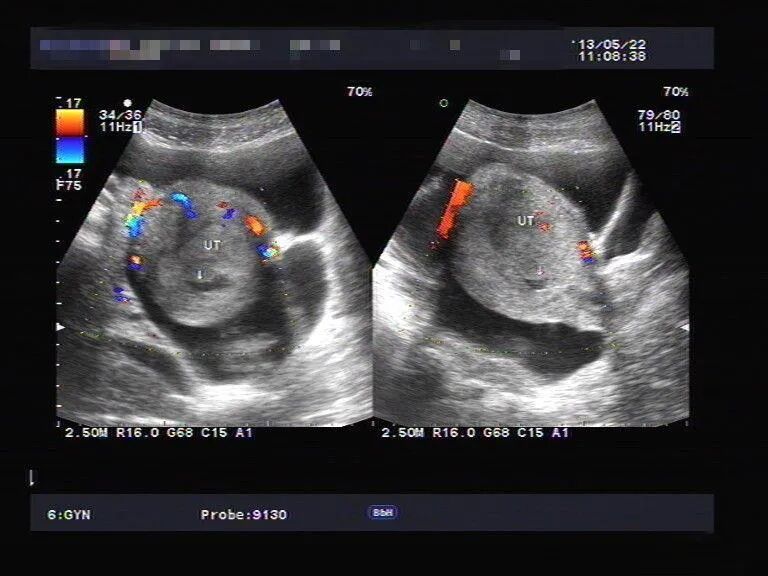

在试管婴儿的过程中由于个人体质不同,有些人可能会在取卵或者移植后出现腹胀、胸闷以及憋气,水肿等腹水症状。

总的来说,取卵后出现腹水的症状,是试管婴儿治疗过程中较为常见的并发症。

准妈妈们遇到这种情况时不必惊慌,症状较轻时,按照医嘱饮食,症状一般在几天内就会减轻或消失。如果症状较严重,应立即就医,进行相应治疗,争取早日康复。